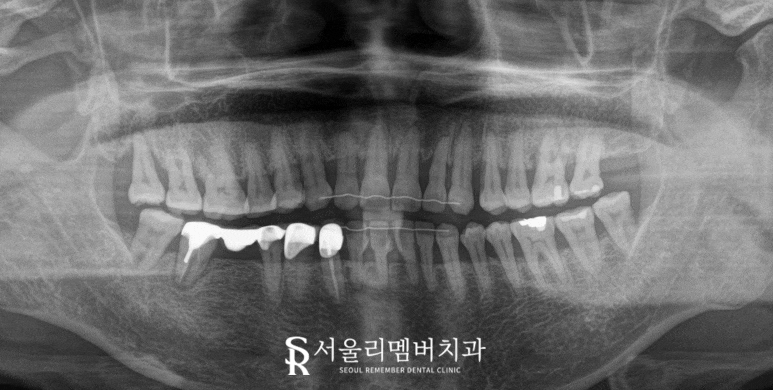

육안으로 확인된 문제 이외에도

보이지 않는 치조골 내

상태 파악을 위해

파노라마 엑스레이를 찍어봐야합니다.

왜냐하면 파노라마 엑스레이를 찍으면

이렇게 치조골의 높이는 물론이고

치아 뿌리를 잡아주는

주변 조직의 상태 및

보철 내부 자연치의 상태 등

많은 정보를 알 수 있습니다.

먼저 입안을 보면

오른쪽 아래 구치부에 다수의

문제가 생겨있습니다.

순서대로 살펴보면

먼저 43번과 44번 치아는

오래된 보철로 덮여있으나

음식이 자주 끼면서

주변 잇몸이 붓고,

그 뒤 45번부터 47번까지는

오래된 브릿지가 닳아서

내부 금속이 비쳐 보이고 있습니다.